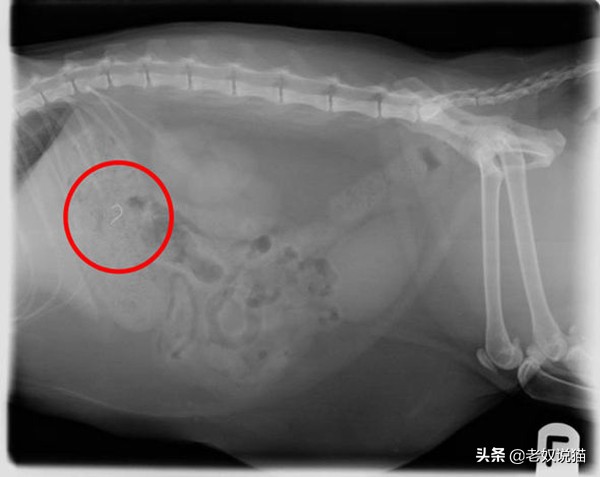

二、误食发圈的猫

美国一只叫Winnie的猫误食46根发圈